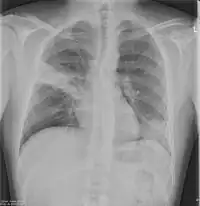

Chest X-rays and X-ray computed tomography (CT) can reveal areas of opacity (seen as white), indicating consolidation.[13] CAP does not always appear on x-rays, sometimes because the disease is in its initial stages or involves a part of the lung not clearly visible on x-ray. In some cases, chest CT can reveal pneumonia not seen on x-rays. However, congestive heart failure or other types of lung damage can mimic CAP on x-ray.[15]

When signs of pneumonia are discovered during evaluation, chest X-rays and examination of the blood and sputum for infectious microorganisms may be done to support a diagnosis of CAP. The diagnostic tools employed will depend on the severity of illness, local practices and concern about complications of the infection. All patients with CAP should have their blood oxygen monitored with pulse oximetry. In some cases, arterial blood gas analysis may be required to determine the amount of oxygen in the blood. A complete blood count (CBC) may reveal extra white blood cells, indicating infection.

X-ray findings indicating hospitalization include: